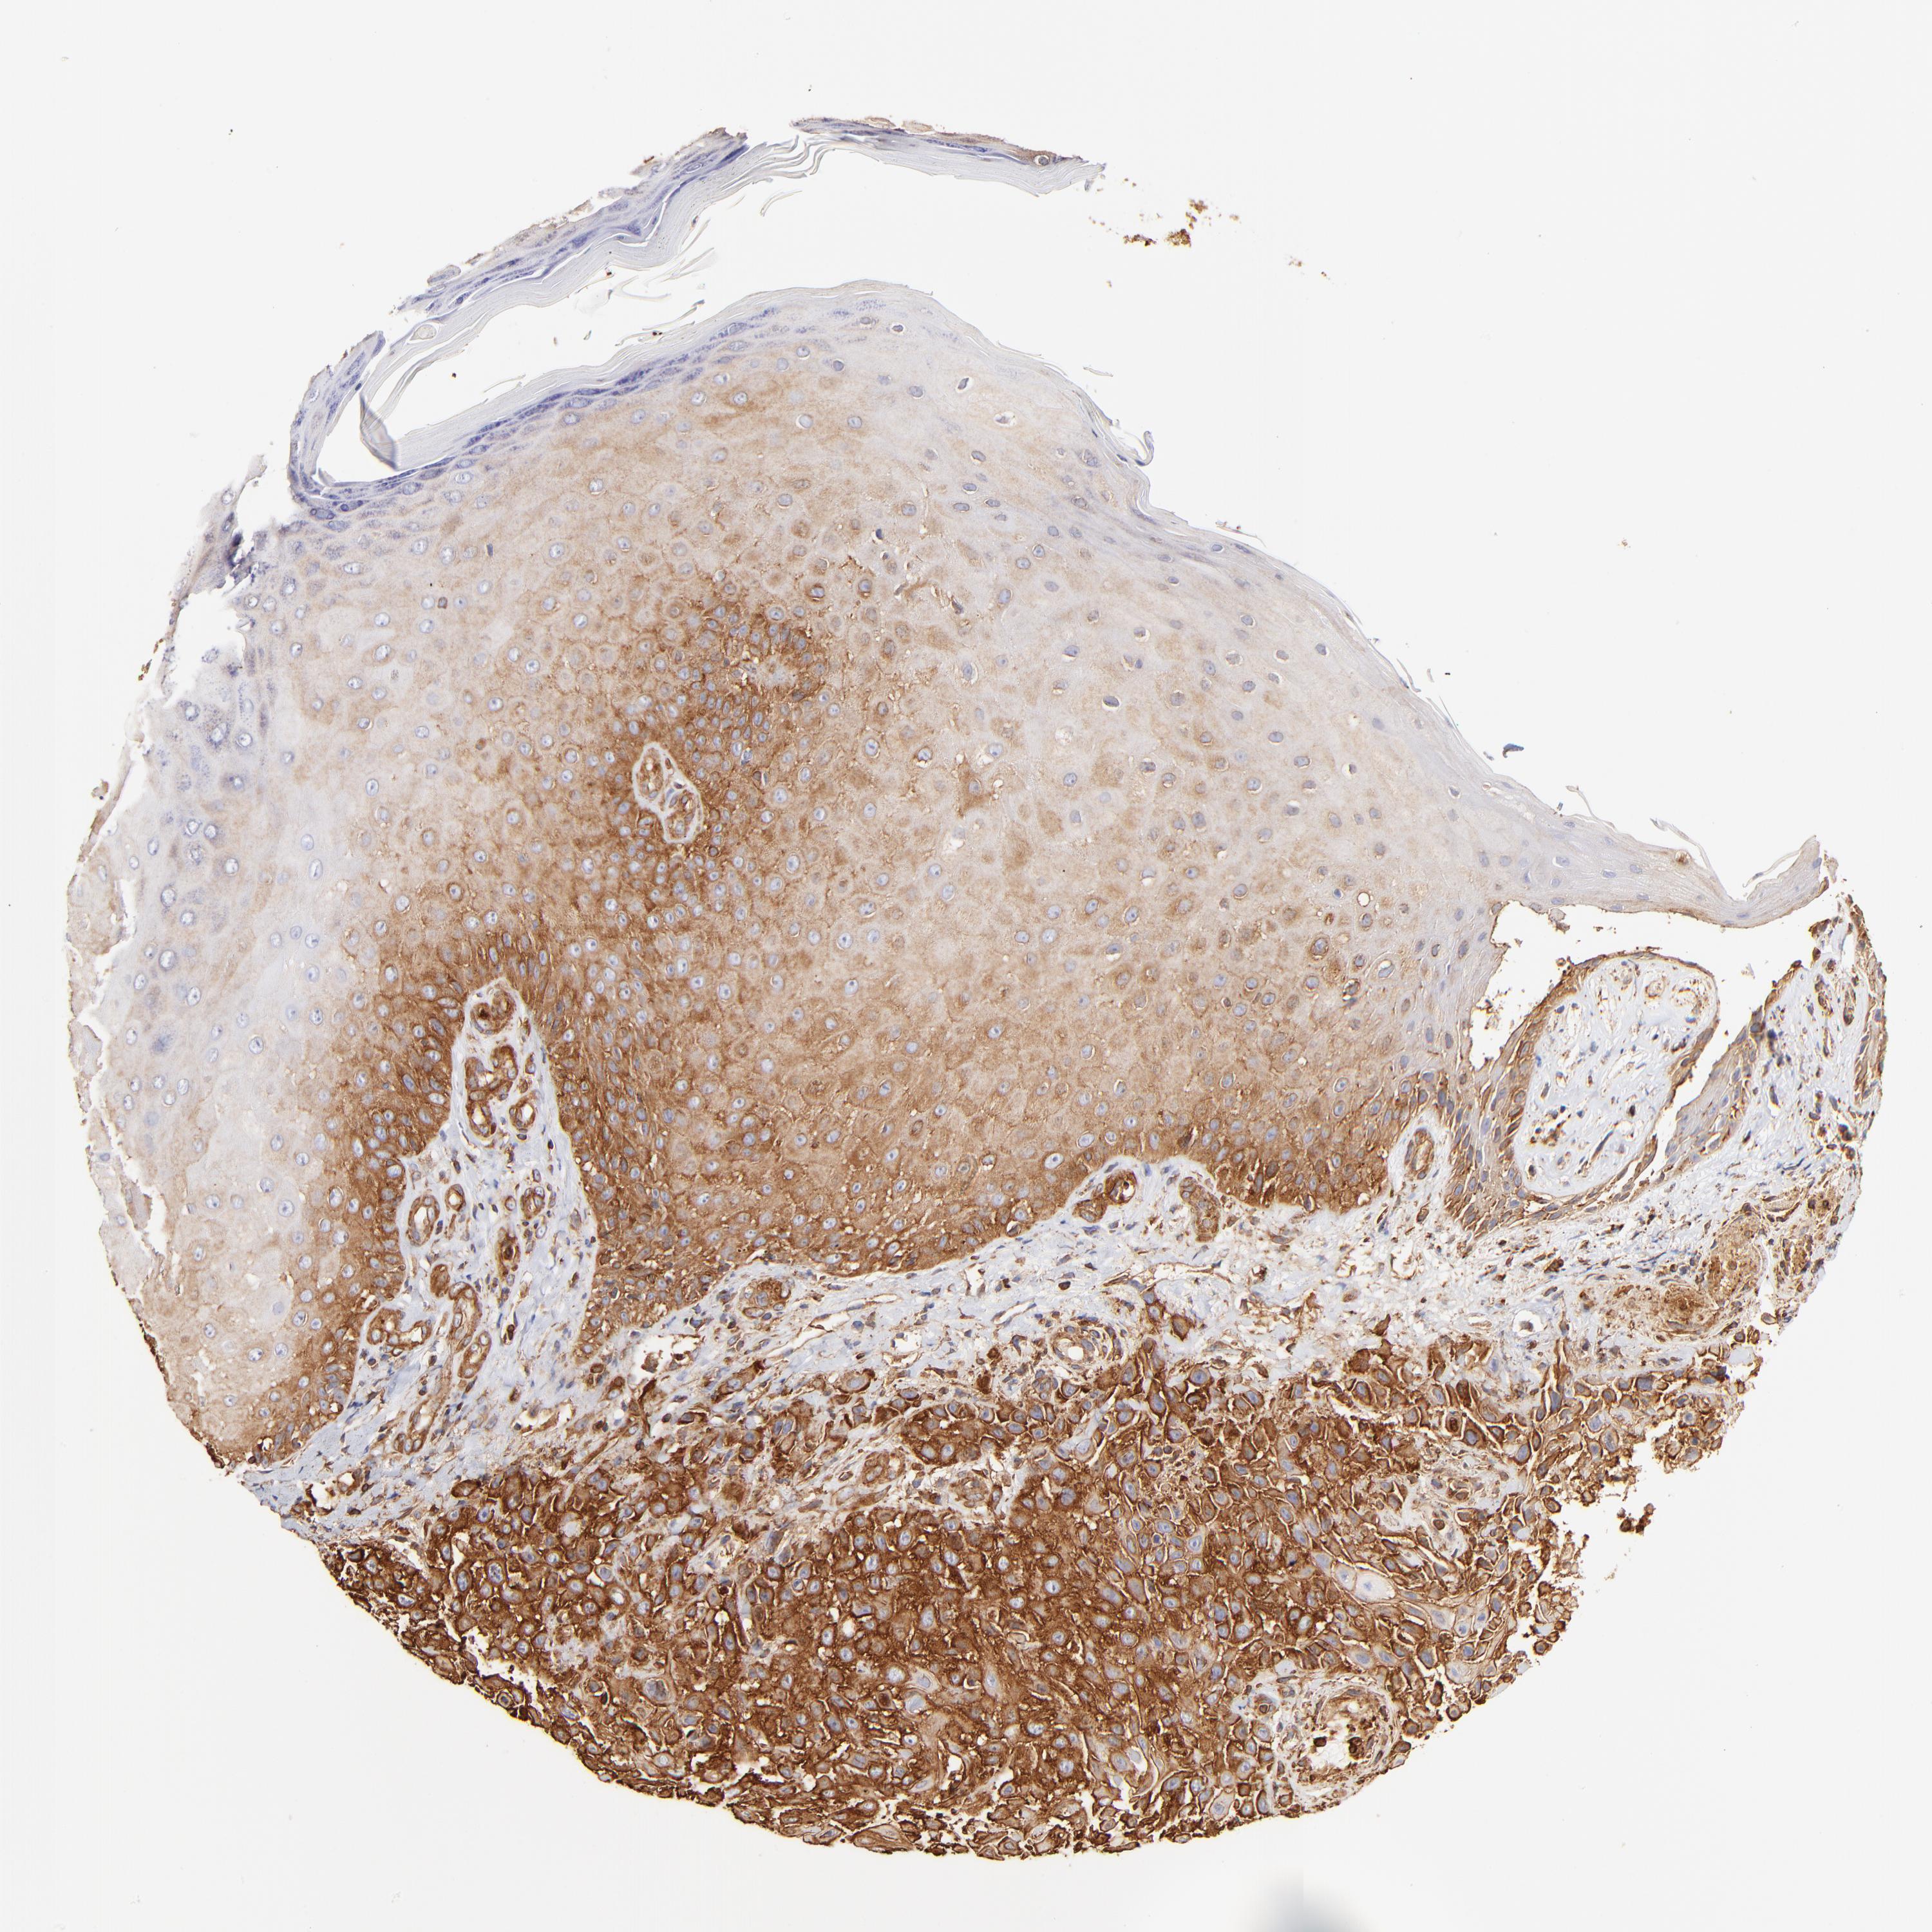

SKIN CANCER - Protein expressioni

A mouse-over function shows sample information and annotation data. Click on an image to view it in a full screen mode. Samples can be filtered based on level of antibody staining by selecting one or several of the following categories: high, medium, low and not detected. The assay and annotation is described here.

Antibody stainingi

Antibody staining in the annotated cell types in the current human tissue is reported as not detected, low, medium, or high, based on conventional immunohistochemistry profiling in selected tissues. This score is based on the combination of the staining intensity and fraction of stained cells.

Each image is clickable and will lead to virtual microscopy that enables deeper exploration of all samples and also displays staining intensity scores, fraction scores and subcellular localization as well as patient and tissue information for each sample.

Antibody HPA001115

Antibody HPA002925

Antibody CAB000356

Staining

High

Medium

Low

Not detected

Intensity

Strong

Moderate

Weak

Negative

Quantity

>75%

75%-25%

<25%

None

Location

Nuclear

Cytoplasmic/membranous

Cytoplasmic/membranous,nuclear

Squamous cell carcinoma, NOS

Basal cell carcinoma